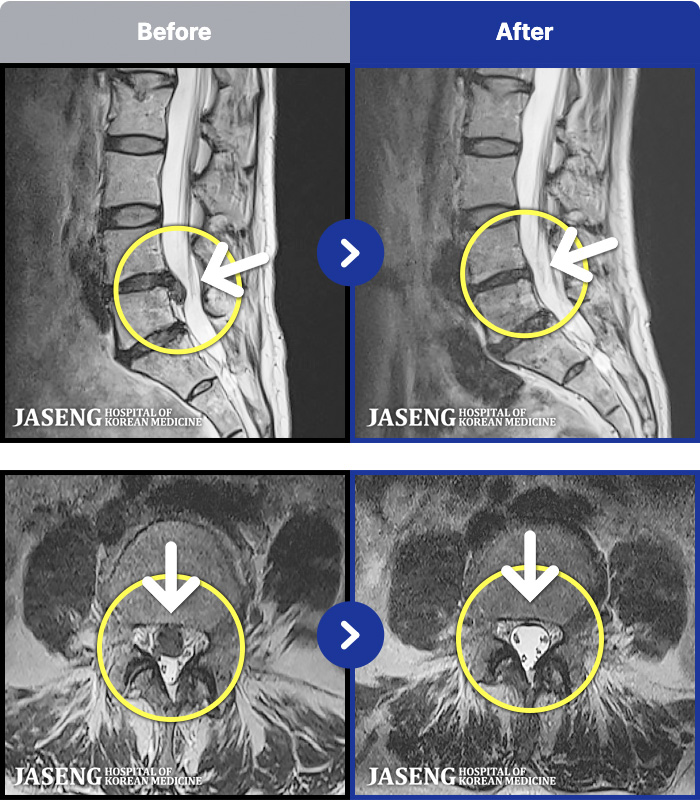

1,301 MRI ũ ʸ Ȯϼ.